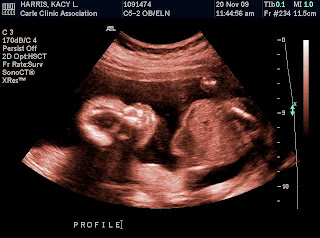

I didn't get a lot of "good" sonogram pictures, but I had to post a couple! We saw so many good views of his face, but we just couldn't get him to stay still long enough for a picture! (I am sure some things will never change!)

My personal fave... his sweet little profile picture....